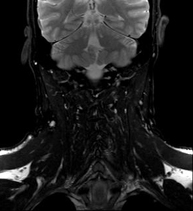

Prueba diagnóstica no invasiva que consiste en la obtención de imágenes de alta definición anatómica del cuello mediante el empleo de un campo electromagnético y ondas de radio (con un emisor y un receptor). No utiliza radiación ionizante. Indicaciones: sospecha de tumor, infecciones, ganglios. - Angio-RM intracraneal

Prueba diagnóstica no invasiva que consiste en la obtención de imágenes de alta definición anatómica de las arterias carótidas y vertebrales a nivel de cuello, mediante el empleo de un campo electromagnético y ondas de radio (con un emisor y un receptor). No utiliza radiación ionizante. En la mayoría de los casos es necesario el empleo de contraste paramagnético (Gadolinio). Permite un estudio angiográfico no invasivo gracias a la inyección de Gadolinio con posterior reconstrucción en 2D y 3D, gracias a estaciones de trabajo especializadas. Indicaciones: problemas circulatorios cerebrales, síncope. - RM Espectroscopia Cerebral